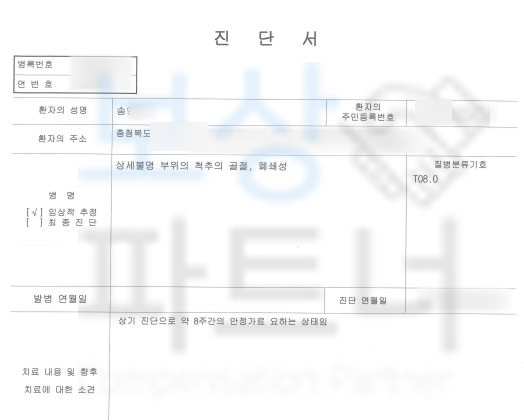

상세불명 부위의 척추의 골절 T08.0

진단을 받으셨꼬 Mri를 찍어보니

요추2번 척추압박골절 확정되었습니다. 주치의는 두달간의 보존치료를 권하였고